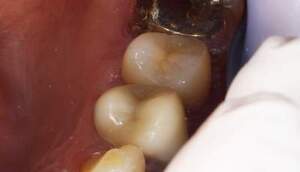

カリエスが大きく、舌側では歯肉より上に残存歯質がなくなってしまっている。このままではコア、クラウンの接着ができないため、歯を歯肉より上にだすことが重要です。

右の写真では歯肉の上に歯が一周のこり、その上にコアが入っているのがわかります。

左上2は広範囲にわたってCRが充填されているのがわかります。またその周囲に透過像があり、カリエスになっていることもわかります。

左は歯を挺出するために装置をつけた直後です。右は挺出が終わり、コアをセットしたところです。歯根の位置が歯冠側によっているのがわかります。